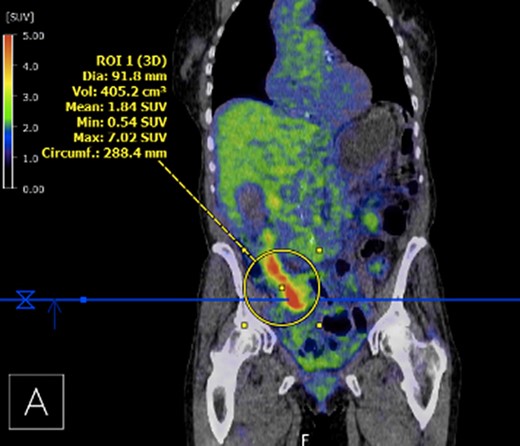

Submucosal biopsies from ascending colon unexpectedly demonstrated metastatic carcinoma consistent with female genital tract origin—CK7 positive; CK20 negative; PAX-8/WT-1/ER/CA125 all positive. A PET/CT was performed on the basis of the histological findings, which demonstrated intense FDG-avidity in the known site of disease in the ascending colon (Figs 2 and 3), as well as a separate focus of increased metabolism in the left pelvic side-wall (Fig. 4), which was presumed to represent an ovarian primary. There was no evidence of nodal or peritoneal disease, however, note was made of mild bilateral hydroureter without clear transition point. CA125 was 118 U/mL (Ref. range 0–35).

PET demonstrating intense metabolic uptake in thickened ascending colon.